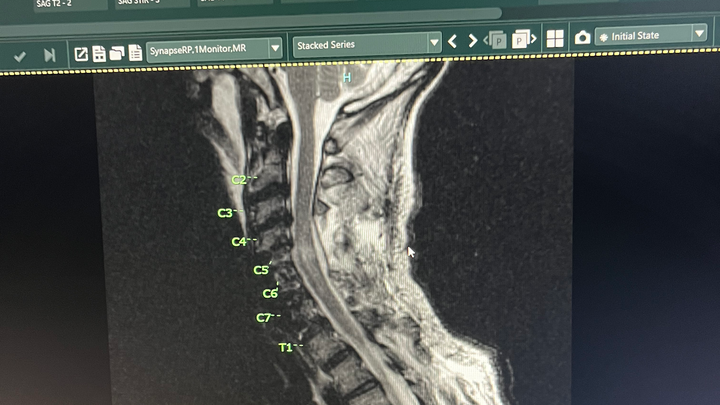

On the day of a routine medical procedure fusing together C4 C5 and C6, previously C5 C6 and C7 were fused during the procedure C3 as well needed to be fused as a result of this, complications occurred that resulted in spinal cord injury and loss of motor function. Mr. Fisher is under the care of his treating physicians and specialty consultants. Medical records and procedure summaries have been secured and are being reviewed by his care team and independent specialists to define the cause, the precise neurologic level and extent of injury, and the timelines for decision points about experimental therapies and rehabilitation.

• Before any experimental treatment, protocol eligibility and medical clearances are required: imaging review (MRI/CT), electrophysiology testing, infectious disease screening, and comorbidity clearance. These tests are being prioritized.